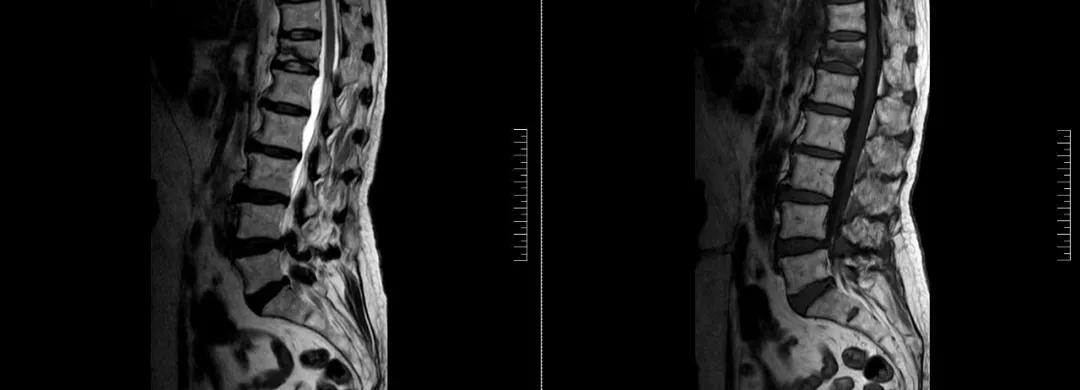

術(shù)前磁共振檢查提示腰1椎體新鮮壓縮性骨折

術(shù)后復查CT可見骨水泥彌散充分